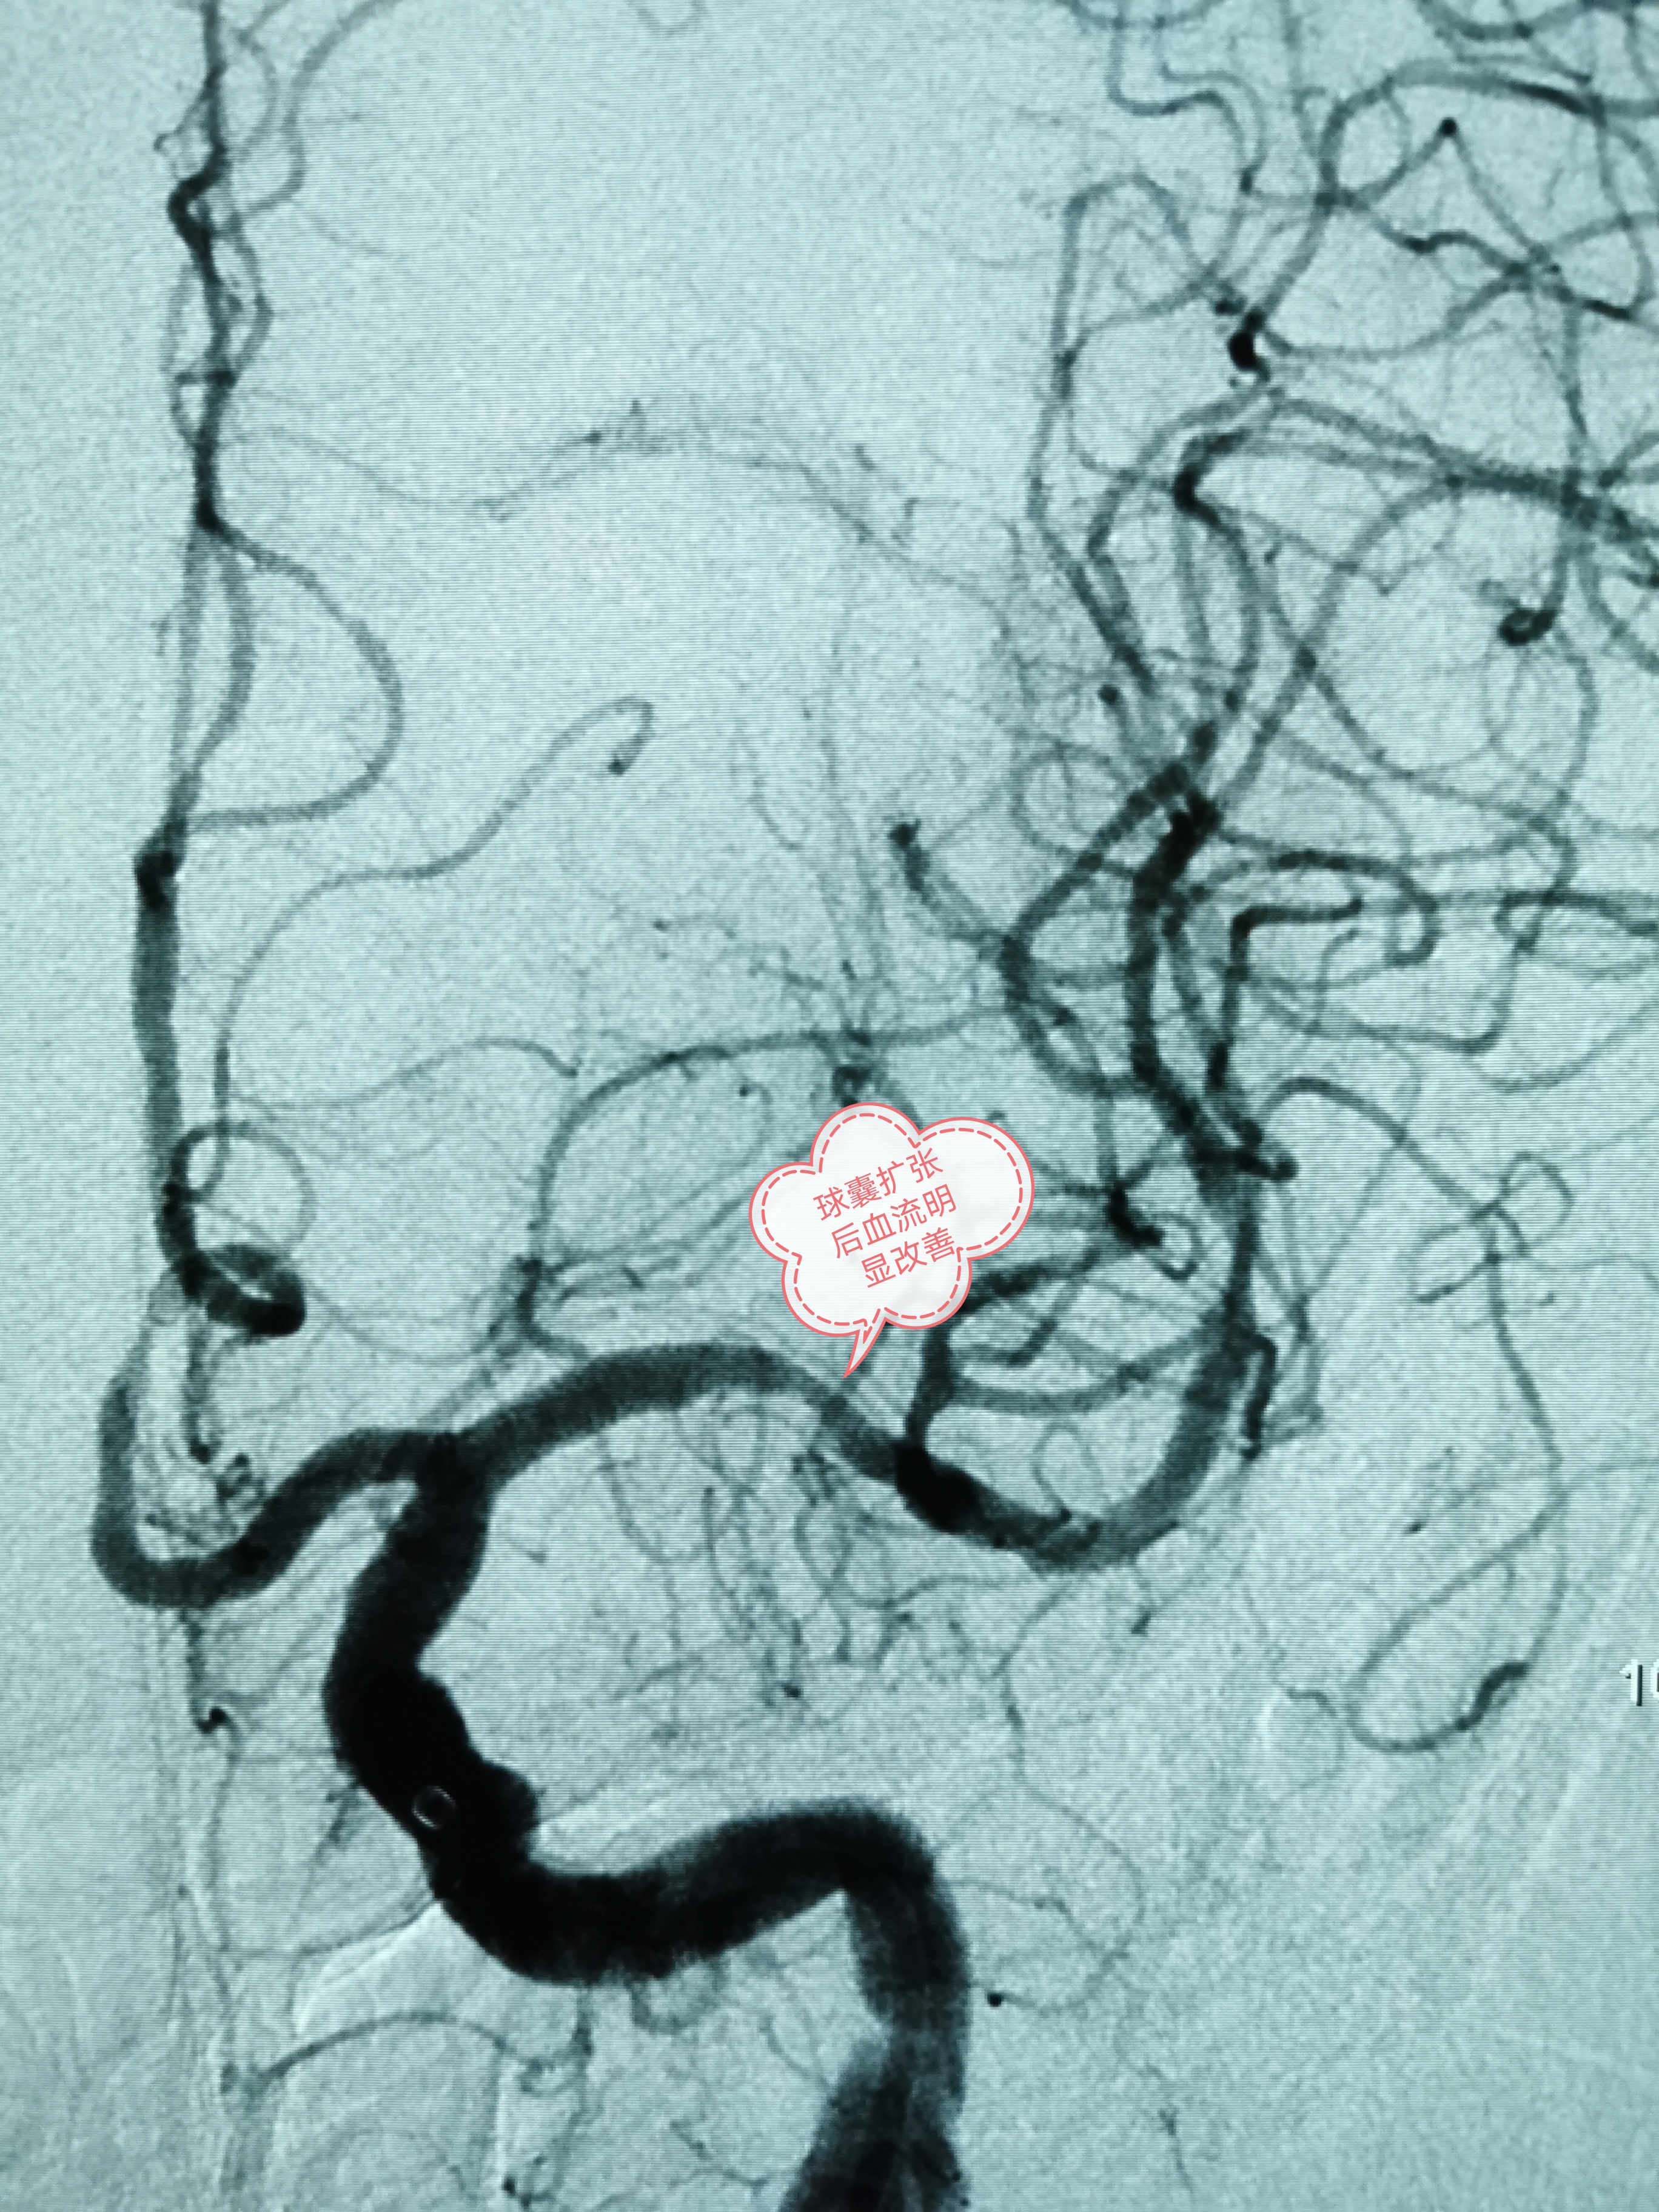

球囊扩张后血流明显改善

经过细致的术前准备后,班先生被送入介入导管室进行手术。术中发现班先生右侧颈内动脉一夹层动脉瘤,长14.4mm×高6.2mm,瘤颈宽10.8mm,合并左侧大脑中动脉重度狭窄。韦仕荣主任经过精细操作在患者右侧颈内动脉夹层动脉瘤处置入Tubridge血管重建装置,精确到位,即刻造影可见病变血管的血流形态明显改善。之后在左侧大脑中动脉重度狭窄处予球囊扩张成形术,造影显示血管狭窄明显改善,一次手术解决了两处重大的脑血管病变,手术过程顺利,且无并发症发生。次日班先生即可正常活动,恢复良好,术后第5天即康复出院。